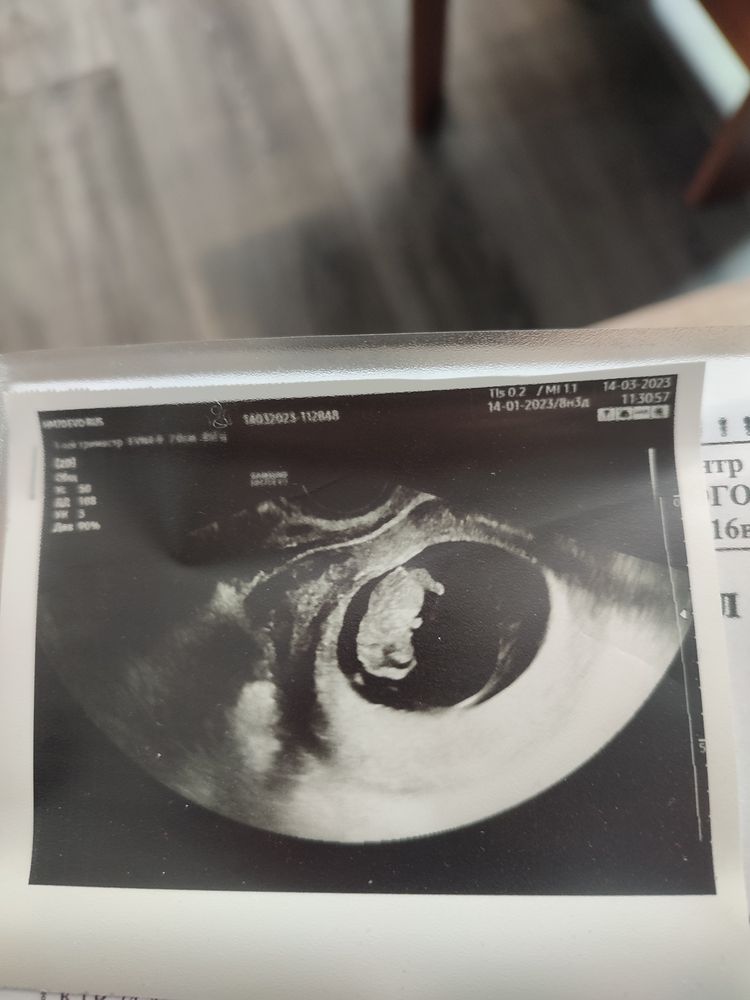

УЗИ в 8 недель после госпитализации.

УЗИ, КТГ, доплерДевочки добрый день! Пишу просто поделиться. Последние м 14.01.23 (а они ли были? 🤷♀️). Срок на сегодня 8 недель 4 дня (акушерских). 17.02 загремела в отделение с кровянистыми выделениями алого цвета - 2 пятна на ежедневке. Я в панике, врач успокаивает, назначают капельницы, кровоостанавливающее, ношпа и Дюфастон. Через 2 дня не кровит, еще через 3 - коричневые выделения единожды и не много. Выписали домой лежать. Сегодня ходила на узи - всё хорошо 🙂, малыш развивается но по ктр (24,4 мм) срок на 9 недель ну или просто крупный как сказал врач. А еще сказали: "срок ещё маленький, но скорее всего мальчишка 🙈. Но не точно. Может ещё всё изменится 🤣". Поживём - увидим. А может и правда, не зря ж мне сегодня приснилось что мне подарили большой синий атласный бант! Всех обнимаю 💋😁